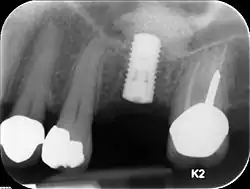

Unterkiefer

Im Unterkiefer ist die Höhe des Kieferknochens nach kaudal durch den Nervus mandibularis begrenzt. Dieser darf nicht tangiert werden, weil es sonst zu bleibenden Sensibilitätsausfällen insbesondere im Bereich der Unterlippe und des Kinns kommen kann. Die Mindestlänge eines Implantats beträgt 8 mm, wobei Implantatlängen von 10 bis 12 mm angestrebt werden. Reicht diese Höhe nicht aus, muss ein Knochenaufbau durchgeführt werden. Ähnliches gilt für einen nicht ausreichend breiten Kieferkammknochen, in den das Implantat eingebracht werden soll.